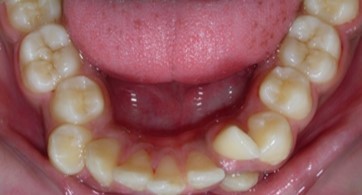

Intraoral assessment. (Figure 1d,Figure 1e,Figure 1f,Figure 1g,Figure 1h).

Figure 1h.Pre-treatment intra-oral-Lower occlusal

The maxillary arch was V-shaped with severely proclined and rotated maxillary incisors with a palatally placed 12. The mandibular arch was U-shaped with severe crowding of mandibular incisors, with 43 partially erupted and buccally placed with transpositioned 42 and 43, with 42 mesiolingually rotated, 33 distolingually rotated and 34 distolingually rotated and buccally placed.

Severe increase in overjet and deep bite were both observed. The maxillary midline coincided with the skeletal midline but the mandibular midline was shifted to the right side by 1 mm. Bilateral maxillary posterior crossbite was also observed. On right side the molar relation was Class I and on the left side it was Class II. The canine relation was Class II on the left side and the curve of Spee was increased.